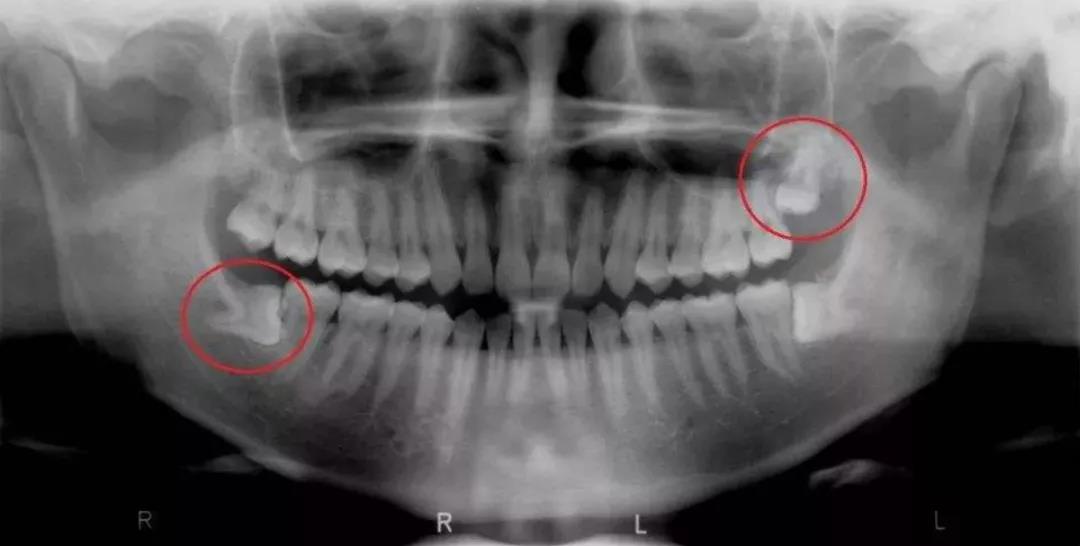

第二种是去医院拍CBCT牙齿全景影像片,通过专业的设备,可以很好的显示整口牙齿的分布状态,直观地看到自己有没有智齿,以及智齿的生长情况。

因为即便你的智齿没有萌出,肉眼无法看到,但在设备和片子里却可以明显地看出智齿在牙槽骨中位置,判断它是否会对口腔健康产生威胁。